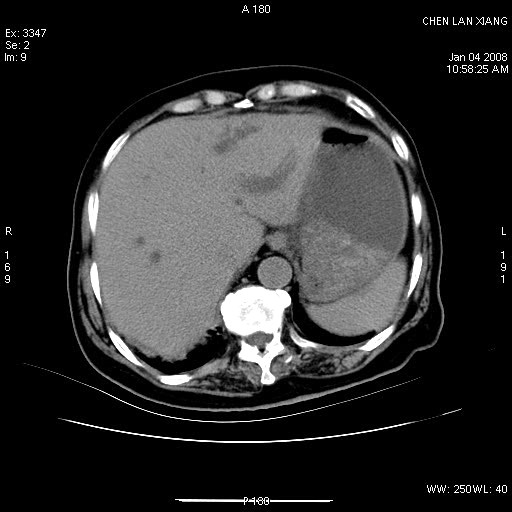

女,76岁,腹痛3-4天,b超示:肝内实性肿物,胆囊强回声,胆总管扩张.

考虑:1、胆总管下端结石伴梗阻性肝内外胆管扩张(肝左叶外侧段肝内胆管多发结石、胆管炎);

2、肿囊癌累及肝,不除外 黄色肉芽肿性胆囊炎。

1 胆总管末端结石伴肝内胆管结石,肝内外胆管扩张。2 胆囊扩大,胆囊壁不规则增厚,内见软组织密度影。考虑:慢性胆囊炎,不除外胆囊癌!

ct所见:1、 肝内胆管结石,肝内外胆管扩张。低位胆道梗阻,胆总管下端结石;2 胆囊扩大,胆囊壁不规则增厚

考虑:胆总管下端结石并肝内外胆管扩张,肝内胆管结石;

慢性胆囊炎

标题: 肝右叶病灶

胆囊癌侵犯肝右叶?

1)胆囊癌伴肝脏转移。2)胆总管下端结石、肝内胆管结石伴肝内外胆管扩张。